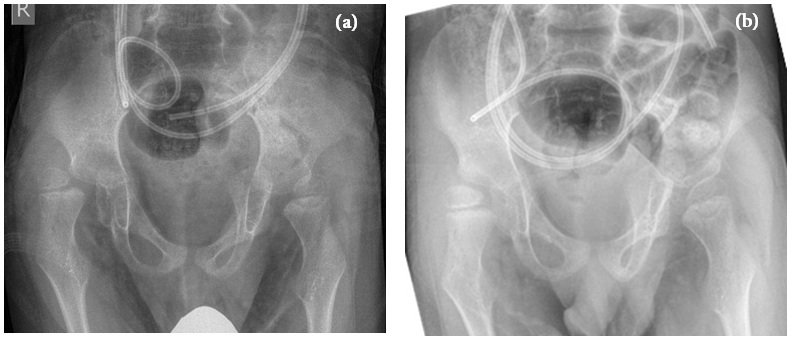

Figure 3: (a) Boy GMFCS 5, 5-years-old, pre OP. (b) Boy GMFCS 5, 14 months postmyofasciotomy.